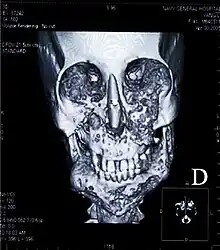

Exemple de chérubisme,

avec forte expansion de la mandibule pouvant conduire à l'apparition d'une « bulle » et à des renflements bilatéraux du maxillaire

(tomodensitométrie en 2D,

femme de 41 ans d'origine chinoise).